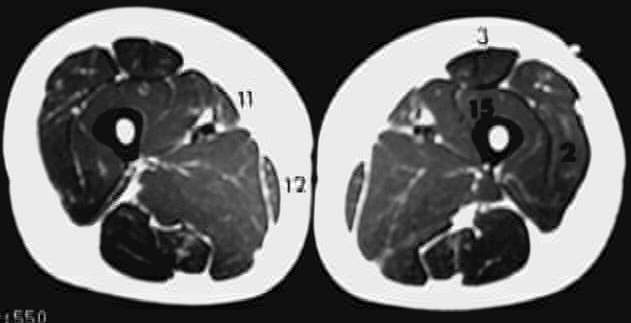

Lower Limbs: Thigh Cross Zoom 1 of 2